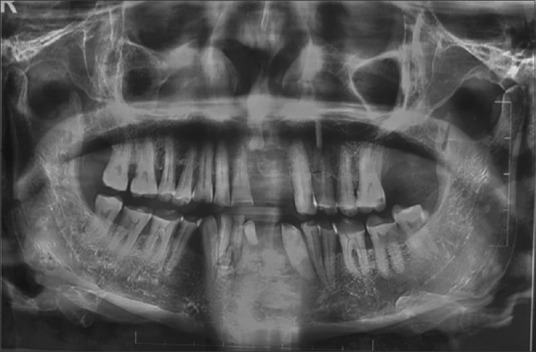

Osteochondroma (OC) is the most common benign tumour of the axial skeleton which often occurs from the metaphysis of the long bones but rarely occurs in the craniofacial region (<1% of cases). Literature shows that cases occur more in the mandibular condylar region. To date, only six cases of this incredibly rare OC in the mandibular front region have been documented in the last 30 years. In addition to reviewing the literature on OCs of the mandibular front region, this case report describes a case of OC involving the mandibular symphysis and left para-symphysis in a 67-year-old male patient. Histopathological examination revealed chondroid and osteoid tissue with sparse fibrous tissue patches and columns of chondrocytes with single tiny nuclei within the cartilaginous cap, and all these features were strongly suggestive of OC diagnosis.